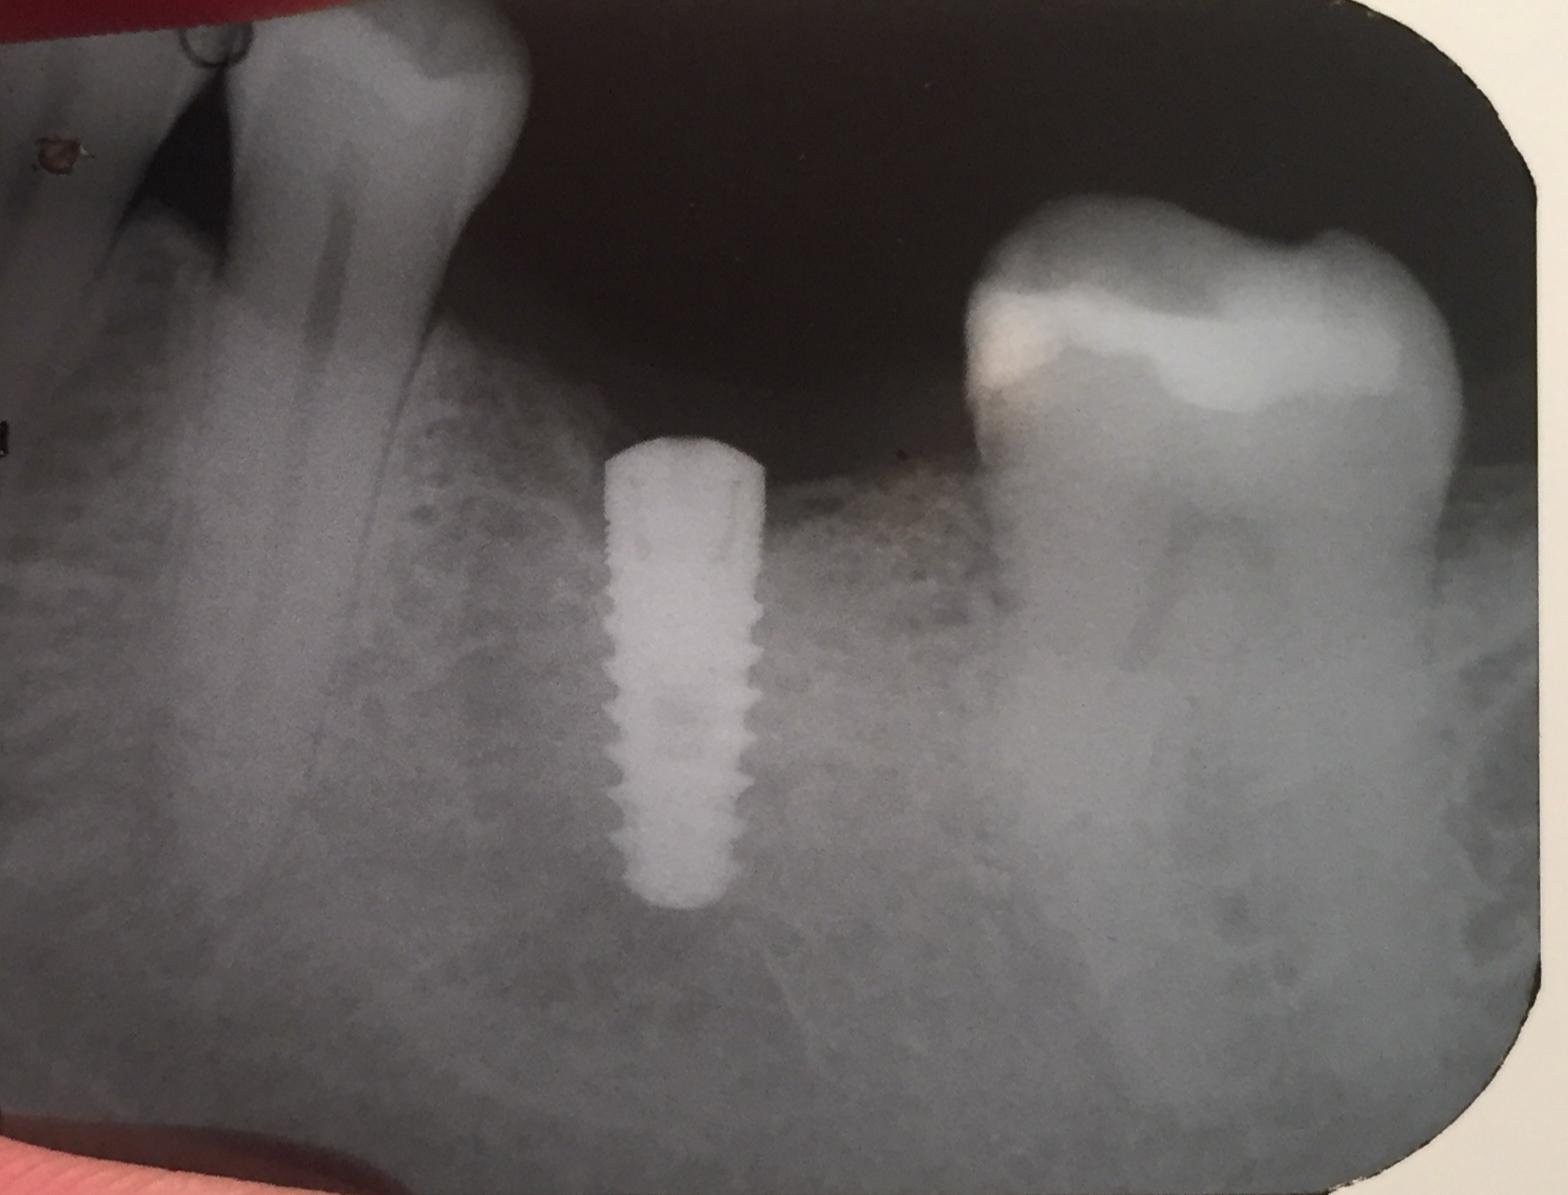

Paciente masculino de 60 años se presenta con un implante dental instalado en la zona de la pieza 36, instalado ya hace un año y nunca se realizo la rehabilitación [...]

No sé de qué implante se trata